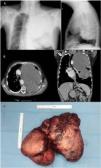

As part of the diagnostic procedure, we performed a computed tomography (CT) scan of the chest, which showed evidence of a left pleural mass measuring 21.5×12×23cm (Fig. 1). Extended clinical laboratory tests were conducted, including liver function tests, electrolytes, thyroid function, and proteins, with results within normal limits. However, the patient showed strikingly poor glycemic control despite a diet high in slow-absorbing carbohydrates and intermittent glucose supplements; for this reason, with the agreement of the endocrinology department, we decided to start treatment with corticosteroids at a dose of 1mg/kg/day. Glucose levels improved, although episodes of severe hypoglycemia persisted, preventing patient discharge. A CT-guided biopsy was performed in the radiology department, with a pathology study result consistent with pleural fibroma markers with positive immunohistochemical markers bcl-2 and CD34 and a proliferation index (Ki-67) of 3–7%. Paraneoplastic syndrome due to the fibrous tumor was suspected, so insulin-like growth factor II (IGF-II) determination was requested, with a result of 621ng/mL (reference values 350–1000ng/mL).

During admission, the patient developed incapacitating pain in the left hemithorax requiring progressively increasing doses of analgesia. Given these symptoms, the thoracic surgery department was contacted and preoperative studies were performed (PET-CT), identifying a pleural mass with a maximum SUV of 5.3g/ml with no uptake at other levels, lung scintigraphy with differential count showing 82.3% perfusion corresponding to the right lung and the remaining 17.7% corresponding to the left lung. In view of persistent hypoglycemia and chest pain, the patient was referred for thoracic surgery and underwent complete resection of the pleural tumor by thoracotomy, preserving the pulmonary parenchyma in its entirety. After the operation, the patient's steroid treatment was progressively tapered, with normalization of blood glucose levels and disappearance of pain.